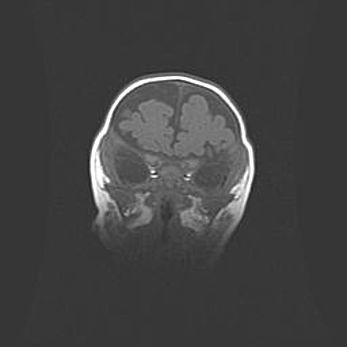

Лейкомаляция с кистозно-глиозной дегенерацией головного мозга.

Возраст: 2 месяца 25 дней

Вес: 6400 г

Окружность головы: 40 см

Срок гестации: 41 неделя

Лейкомаляцию относят к ишемически-гипоксическим повреждениям головного мозга, диагностируемым у новорожденных. При лейкомаляции в головном мозге обнаруживают очаги некроза, возникшие после тяжелой гипоксии и нарушения кровотока. В процессе морфогенеза очаги проходят три стадии: 1) развития некроза, 2) резорбции и 3) формирования глиозного рубца или кисты. Перивентрикулярная лейкомаляция (ПЛ) встречается примерно в 12% случаев среди новорожденных, обычно – у недоношенных детей, причем, частота ее зависит от массы, с которой младенец появился на свет. Наибольшее число малышей страдает лейкомаляцией, если масса при рождении 1500-2500 г.